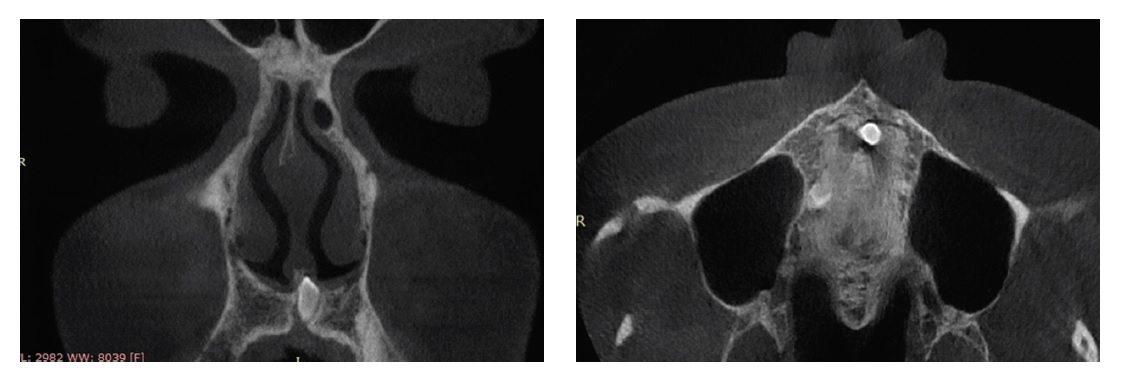

Было принято решение удалить инородное тело дна полости носа под эндотрахеальным наркозом с использованием видеоэндоскопической аппаратуры, риноскопа d=4мм 0°, 45°. При помощи скальпеля выполнен разрез слизистой оболочки дна полости носа слева в передних отделах в проекции образования. Антральной ложкой и щипцами Блексли удалено инородное тело (предположительно сверхкомплектный зуб) (рисунок 4).

Рисунок 4. Сверхкомплектный зуб, удаленный из полости носа. / Figure 4. Supernumerary tooth removed from the nasal cavity.

Зуб находился под углом 45° по отношению к дну полости носа. Перегородка носа не повреждена. Между полостью носа и полостью рта патологического сообщения нет. На слизистую оболочку дна полости носа слева уложена гемостатическая губка. В общий носовой ход слева введен тампон, смоченный в 0,9% растворе натрия хлорида. Кровотечение во время операции незначительное. Послеоперационный период без особенностей. По результатам гистологического исследования – морфологическая картина соответствует строению зуба.